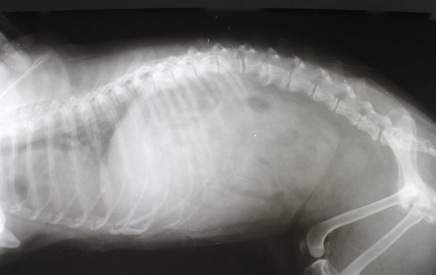

개의 척추와 추간판.

개의 척추는 경추(7개), 흉추(13개), 요추(7개), 선추(3개)와 꼬리꼬리추(6~23개)가 이어져 신체의 축을 형성한다.

척추뼈 안에는 척수가 통과하는 터널 같은 구멍이 있다. 각각의 척추뼈 사이에는 척추를 구부리거나 충격을 흡수하는 쿠션 역할을 하는 조직이 있는데, 이것이 추간판이라고 불리는 것이다.